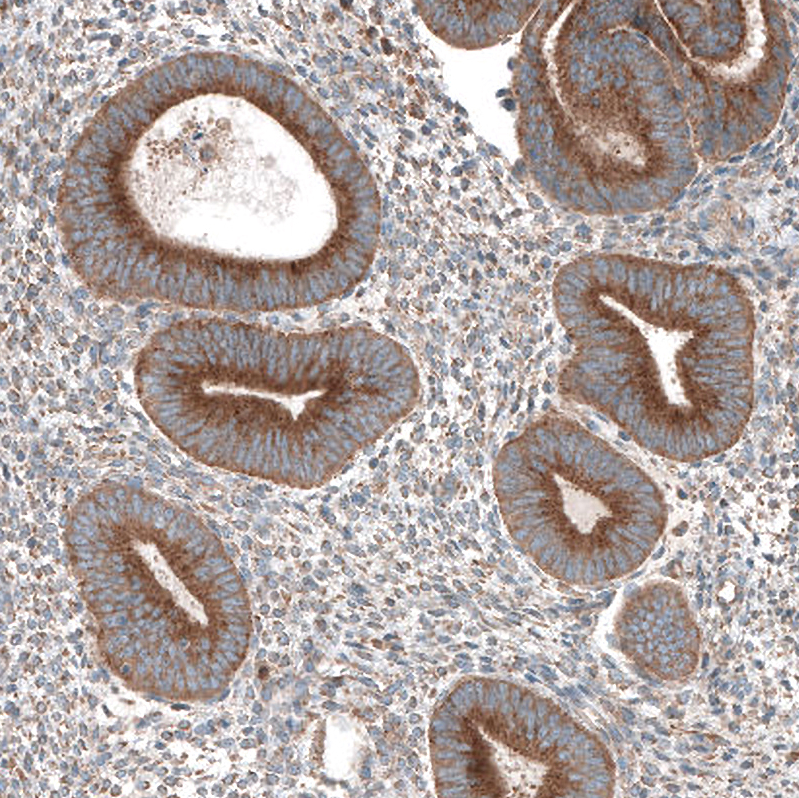

Immunohistochemical staining of human rectum shows moderate granular cytoplasmic positivity in peripheral nerve / ganglion and glandular cells.